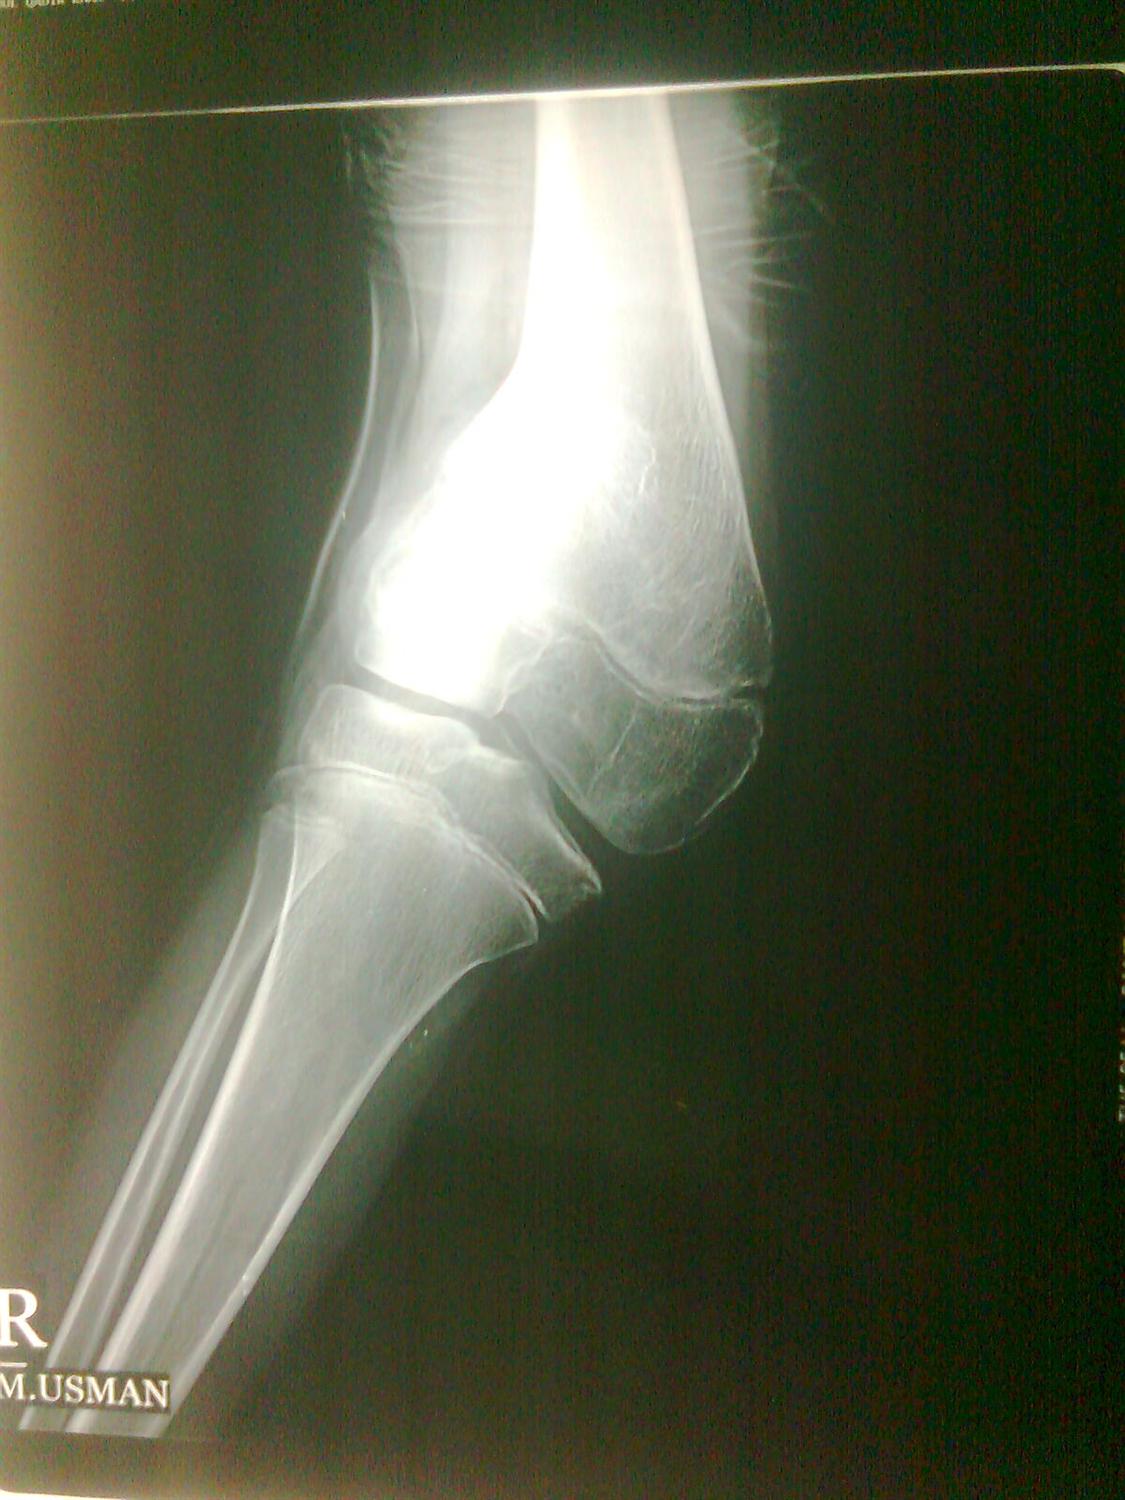

From radiologykey.com

Knee Dislocation Radiology Key What Is A Dislocated Knee A dislocated knee occurs when one of the four bones in the knee joint moves out of position. A knee dislocation, more specifically, is when the bones of the leg (the tibia and fibula) are moved in relation to the bone in the thigh (femur). It’s usually caused by force,. A patella dislocation occurs when the knee cap pops sideways. What Is A Dislocated Knee.